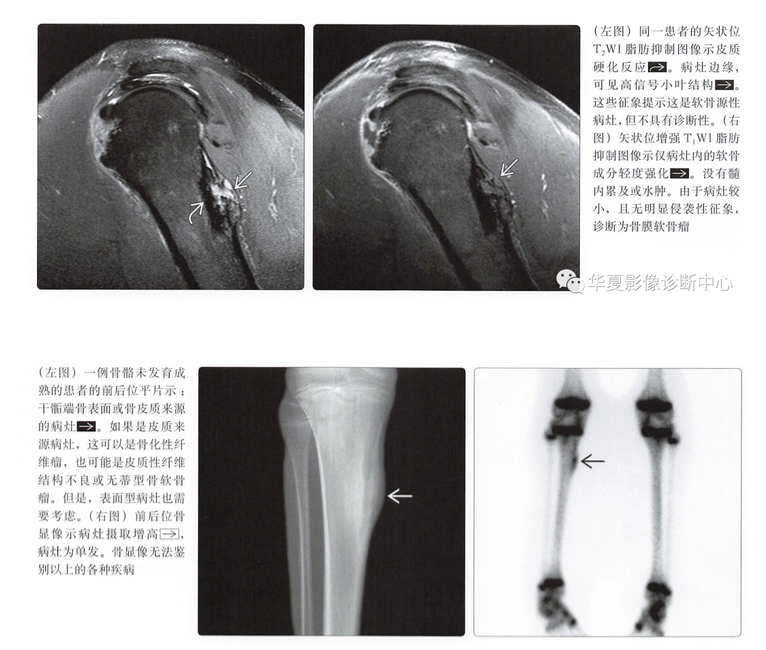

- 平片可以提示本病的诊断,并进行鉴别诊断

- 需要行MR检查以评估软组织和(或)骨髓受累情况

平片表现

- 骨皮质扇形凹陷

- 硬化边

- 致密性骨膜反应,尤其是在病灶近端、远端

- 病灶远端、近端骨皮质杯状改变

- 基质钙化(75%)

- 软组织肿块

- 年龄

- 10~40岁最常见,可发生于儿童